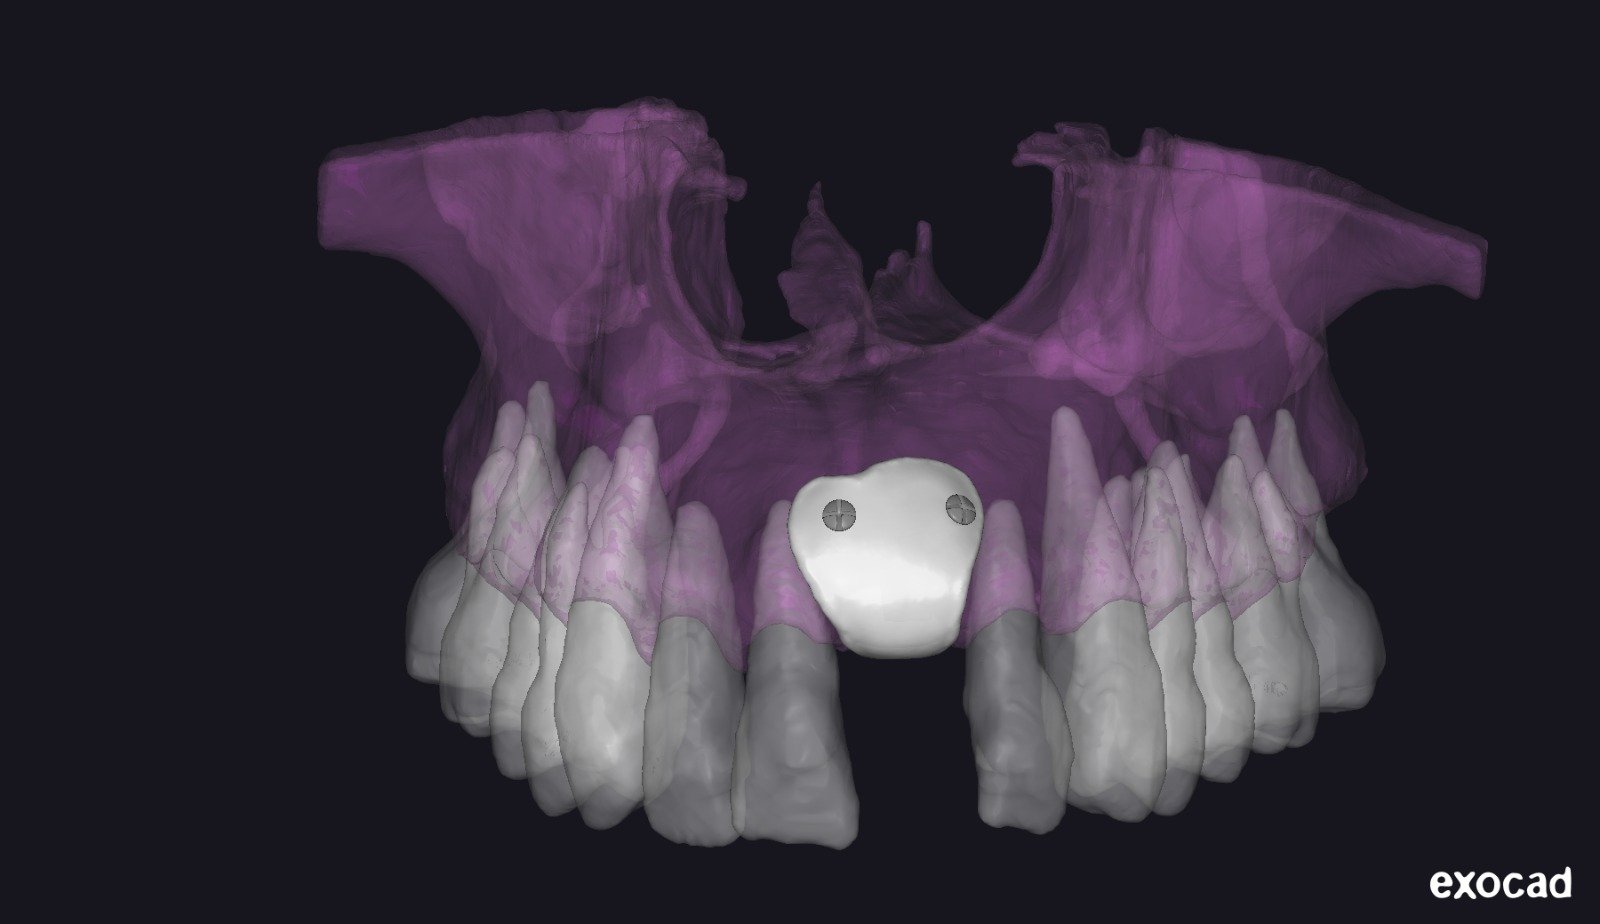

• Introducción al flujo digital en ROG.

• Integración de archivos DICOM, STL y PLY.

• Software utilizados en el protocolo:

• BlueSkyPlan: diagnóstico, segmentación y análisis del defecto.

• Exoplan / Exocad: diseño digital aplicado a la regeneración.

• Meshmixer: ajustes, correcciones y optimización del diseño.

• Segmentación ósea y dental.

• Generación del defecto virtual.

• Control tridimensional del volumen a regenerar.

• Ventajas del diseño realizado por el propio cirujano.

• Concepto de barrera personalizada.

• Principios de diseño biomecánico.

• Espesor, extensión y bordes de la barrera.

• Diseño pasivo y adaptación milimétrica.